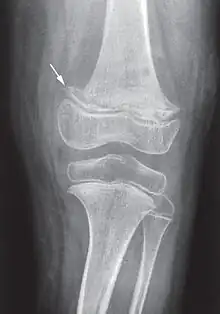

Diagnosis is typically based on physical signs, X-rays, and improvement after treatment.[2]

Various childhood-onset disorders can mimic the clinical and X-ray picture of scurvy such as: